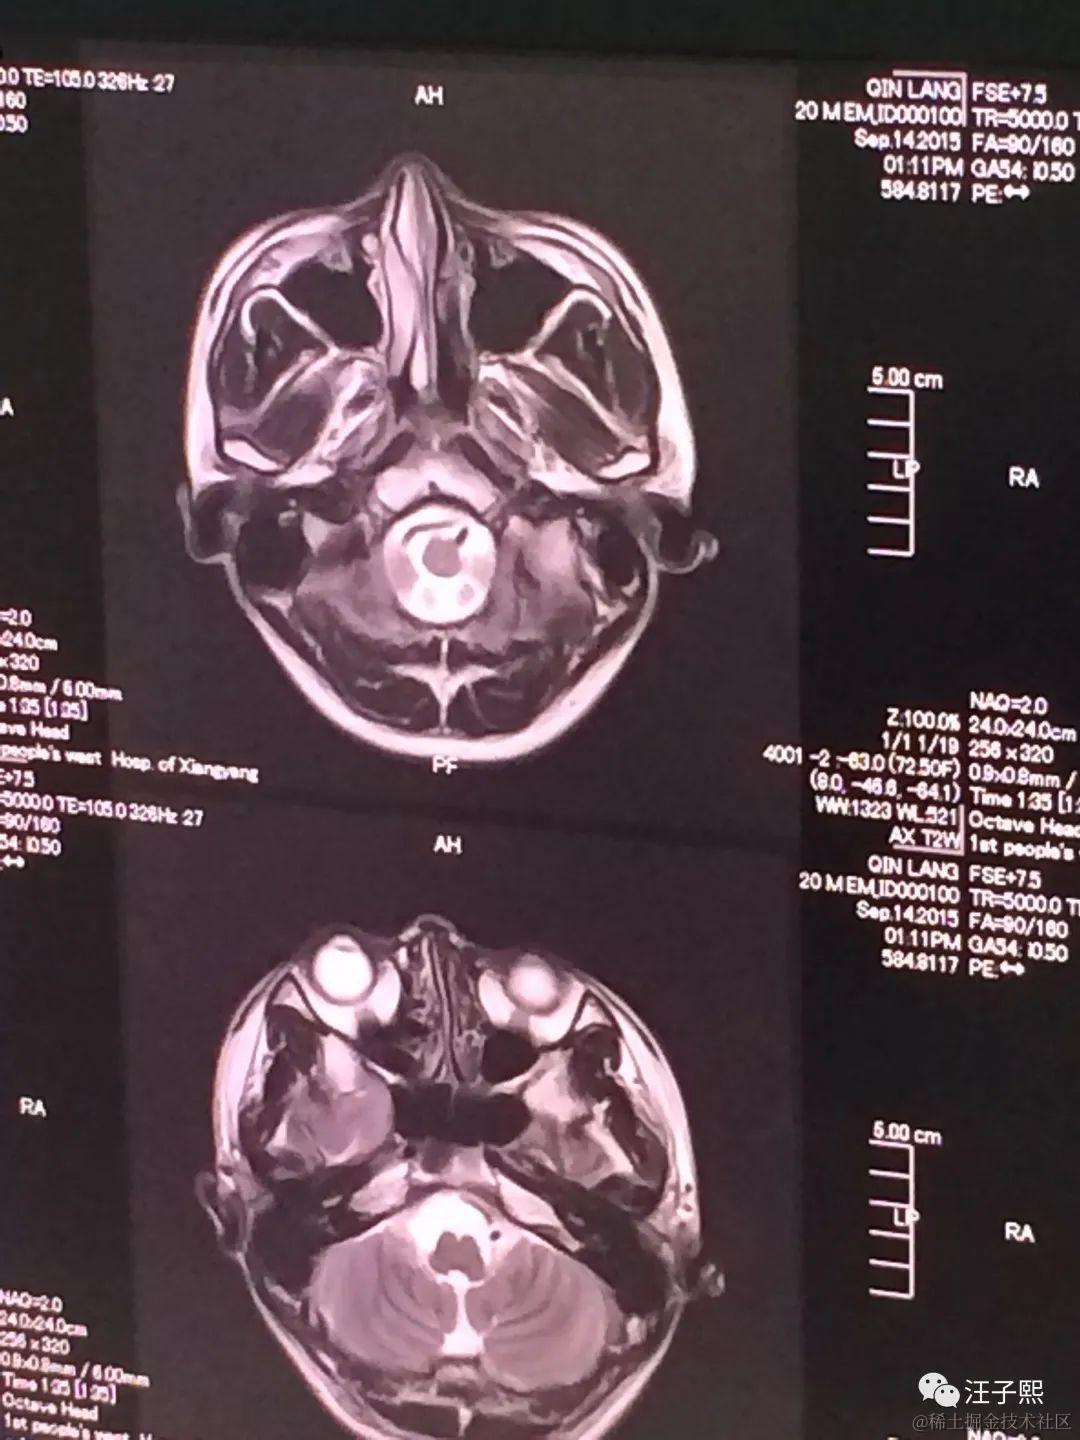

在我注射了造影剂完成了增强核磁共振的检测之后,我静静地坐着,等待护士将我手腕上注射到静脉血管里的针拆下来。